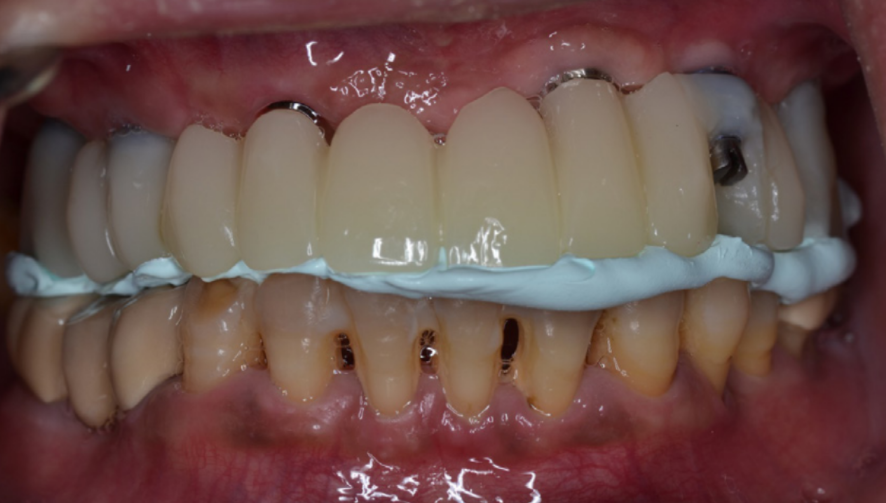

Відфрезерований зразок PMMA було виготовлено і використано для перевірки естетичного вигляду спереду. Мінімальні неточності у встановленій висоті прикусу та центральне змикання було доопрацьовано із використанням матеріалу для реєстрації прикусу. (зображення 15)

15